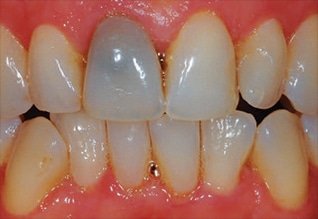

Sbiancamento endodontico

I denti devitalizzati possono essere soggetti a discoloramento col passare del tempo. Con tecniche di sbiancamento intracanalare, ripristiniamo il colore chiaro del dente.